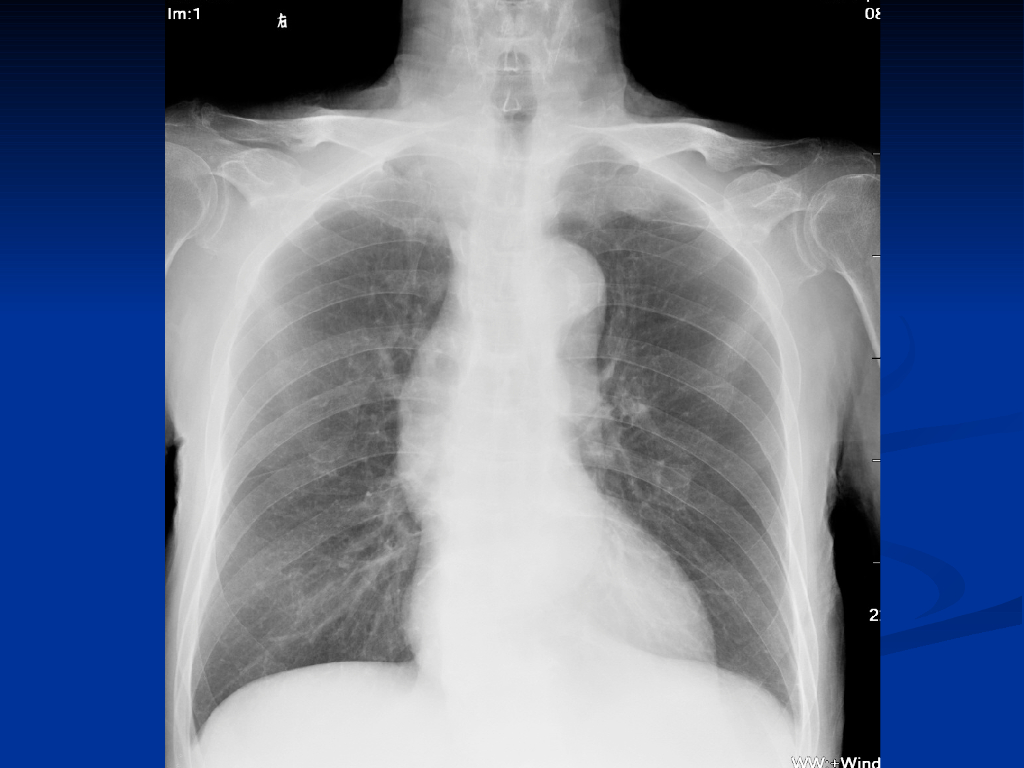

《放射诊断学》循环系统异常影像学表现.pdf